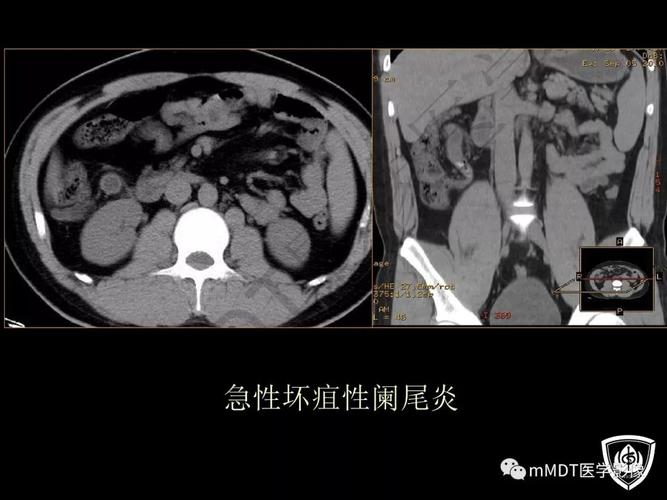

精品讲座急性阑尾炎的ct诊断

ppt急性阑尾炎的ct诊断

全面讲解正常阑尾和阑尾炎的ct表现

开课了急性阑尾炎的ct诊断及鉴别诊断

打基础 | 急性阑尾炎 ct 诊断

急性阑尾炎CT图片